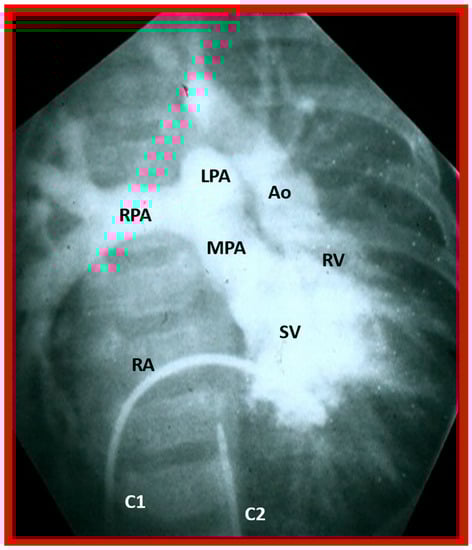

In theory, patients with cardiac malposition may have one (single) or two ventricles. The distinction between one and two ventricles is feasible by echocardiography (Figure 30) and angiography (Figure 31 and Figure 32).

Figure 32. Selected angiographic image in the posteroanterior view of a patient with a single ventricle (SV) illustrating opacification of the main pulmonary artery (MPA) from the main ventricular chamber and the aorta (Ao) arising from a smallish right ventricle (RV). The Ao is situated to the left of the pulmonary artery, signifying the l-transposition of the great arteries. C1. The catheter in the unmarked inferior vena cava was advanced into the right atrium (RA) and then manipulated into the ventricle; C2. Catheter in the unmarked descending aorta. The left pulmonary artery (LPA) and right pulmonary artery (RPA) are labeled. Reproduced from reference [31].

In case there are two ventricles, the question to address is: are the ventricles normally positioned with the right ventricle (RV) on the right side and the left ventricle (LV) on the left side? Or, are the ventricles inverted with morphologic RV on the left side and morphologic LV on the right side? Several methods have been used to make this assessment: